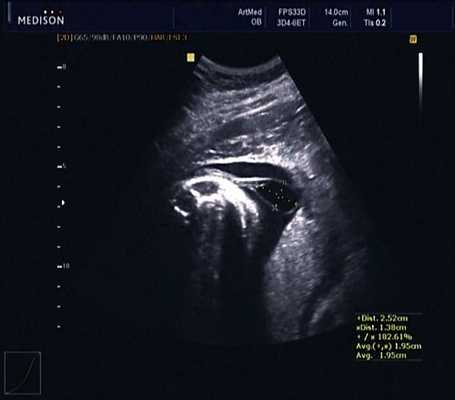

В 30 нед фетометрические показатели плода соответствовали сроку беременности. Сколиотическая деформация позвоночника сохранялась. Дополнительно выявлена оболочечная грыжа, исходящая из грудного отдела позвоночника, в области деформированных позвонков. Грыжа представляла собой стебельчатой формы образование с суженной ножкой (рис. 7, 8). Концевая часть ее была расширена в виде петли и заполнена анэхогенным содержимым (ликвором), которое отчетливо дифференцировалось на фоне "мутных" околоплодных вод (рис. 9). Таким образом, диагноз был уточнен: spina bifida - менингоцеле.

Рис. 7. Беременность 30 нед. Стебельчатая форма менингоцеле.

Рис. 8. Место выхода мозговой оболочки.

Рис. 9. Беременность 30 нед. Эхогенность ликвора ниже эхогенности околоплодных вод.